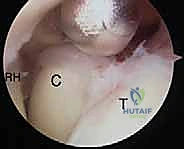

- استكشاف المفصل وإزالة الأجسام الحرة: يتم إدخال الكاميرا وضخ سائل معقم لتوسيع المفصل. يتم البحث عن أي شظايا عظمية أو غضروفية سائبة وإزالتها.

- تحرير المحفظة الأمامية (Anterior Capsulectomy): باستخدام أدوات دقيقة (Shaver & Radiofrequency)، يتم قطع وإزالة الجزء الأمامي من المحفظة المفصلية المتليفة التي تمنع المرفق من المد (Extension).

- استئصال النتوءات العظمية (Osteophyte Resection): يتم استخدام مثقاب دقيق (Burr) لبرد وإزالة الزوائد العظمية في الحفرة الإكليلية (Coronoid Fossa) والحفرة الزجية (Olecranon Fossa) لفتح المجال لحركة العظام.

- تحرير المحفظة الخلفية (Posterior Capsulectomy): ينتقل الجراح إلى الجزء الخلفي من المفصل لإزالة التليفات التي تمنع الثني (Flexion).

- رؤية مكبرة وواضحة: تتيح الكاميرا الدقيقة رؤية زوايا المفصل من الداخل بتكبير عالٍ جداً لا يمكن تحقيقه بالعين المجردة.